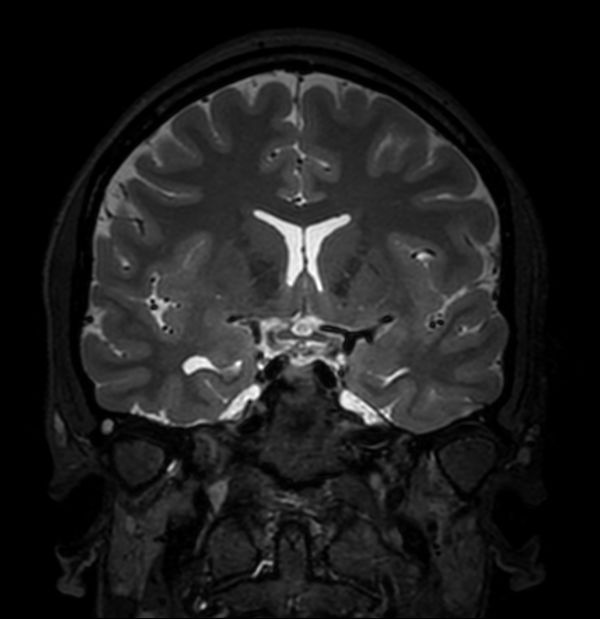

3D T2w TSE (Coronal reformat)

-

Axial 3D T2w TSE DRIVE

3D T2w TSE DRIVE (Coronal reformat)